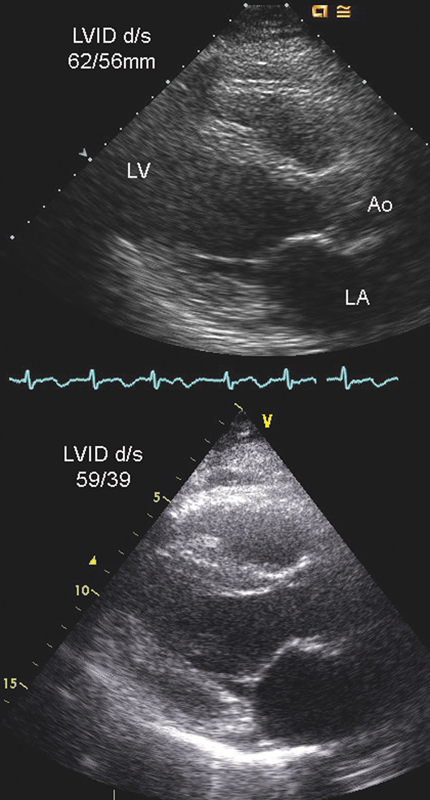

فحوصات تشخيصية لبعض امراض القلب والشرايين التاجية